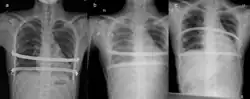

![]() X-Ray of a 15-year-old male after undergoing the procedure | |